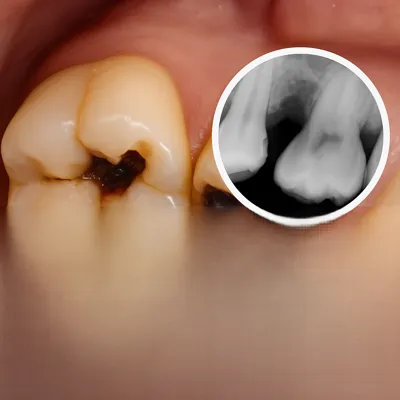

با گذشت زمان، فشار دندان عقل به دندانهای کناری میتواند باعث آسیب به دندان مجاور، پوسیدگی بیندندانی یا تحلیل استخوان موضعی شود؛ مشکلاتی که درمان آنها ساده نیست.

علاوه بر این، هرچه سن بالاتر میرود—بهویژه بعد از ۳۰ سالگی—استخوان متراکمتر میشود و ریشهها تکامل بیشتری پیدا میکنند؛ در نتیجه جراحی سختتر و دورهی نقاهت طولانیتر میشود.

بهدلیل تمیز نشدن انتهای دهان، احتمال گیر غذایی، التهاب لثه، عفونت مکرر و آسیب به دندان مجاور افزایش مییابد.

۹) بهترین سن برای جراحی دندان عقل چه زمانی است؟

در بسیاری از موارد، انجام آن قبل از ۳۰ سالگی سادهتر است؛ با افزایش سن، استخوان متراکمتر و جراحی سختتر میشود.